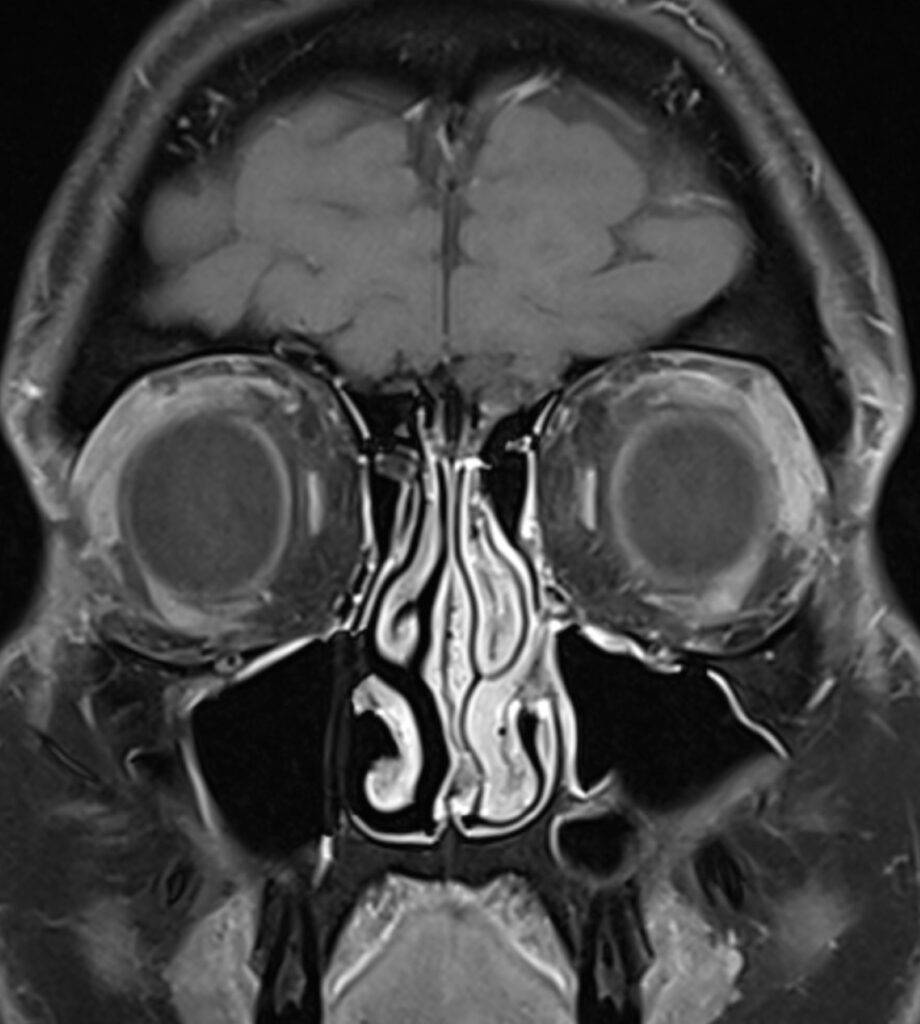

Eine Magnetresonanztomographie des Kopfes, kurz die MRT Kopf genannt, ist ein medizinisch bildgebendes Verfahren. Die MRT Kopf Untersuchung stellt mit Hilfe von Magnetfeldern und Radiowellen insbesondere unser Gehirn, Ohr, Nase und Nasennebenhöhlen, Augen, Kiefer, sowie genaue Strukturen detailliert dar. Vor allem bei diffusen oder langanhaltenden Kopfschmerzen kann eine MRT aufschlussreich sein. Vor allem ermöglicht eine Kopf MRT Einblicke in verschiedene neurologische Erkrankungen.

Eine Kopf MRT liefert Ärzte und Radiologen detaillierte Bilder. Zu sehen sind das Gehirn, Schädelknochen, Blutgefäße und anderer umgebende Gewebe im Kopfbereich.

- Tumore und Zysten: Die MRT Kopf kann sowohl gutartige als auch bösartige Tumore im Gehirn erkennen. Sie kann auch bei der Identifizierung von Zysten und anderen strukturellen Anomalien helfen.